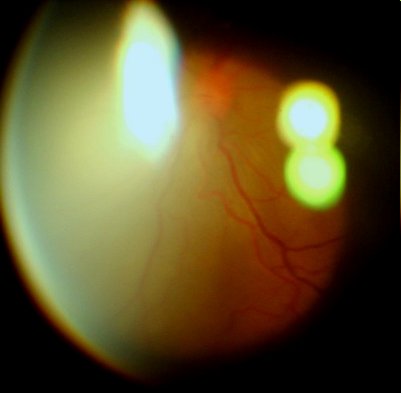

眼底像(前节照相机+90D,图像质量不高,见谅)

此主题相关图片如下:

周边视网膜渗出性脱离隆起